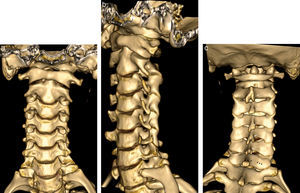

Anatomía de la columna cervical en tomografía computarizada multidetector con con reconstrucciones volumétricas. a) Vista coronal anterior donde se visualizan las articulaciones uncovertebrales y el incremento progresivo del tamaño de los cuerpos vertebrales. b) Vista oblicua (online), que permite la identificación de los agujeros de conjunción. c) Vista posterior (online) las apófisis espinosas, que son bífidas de C2 a C6 (flecha blanca) y mayor en C7, así como las láminas (puntas de flechas negras).

Tomografía computarizada multidetectorEl desarrollo de las nuevas técnicas de tomografía computarizada multidetector (TCMD) han permitido la adquisición de volúmenes isotrópicos que permiten reconstrucciones volumétricas y multiplanares con igual resolución en todos los planos. Su papel en el estudio de la patología degenerativa se ha incrementado de forma significativa debido a su gran resolución espacial, permite valorar el componente óseo osteofitario y la calcificación del LLP, así como la valoración del compromiso del agujero de conjunción. En algunos centros y cada vez más se considera una herramienta útil de forma prequirúrgica complementaria a la RM (fig. 3)10.